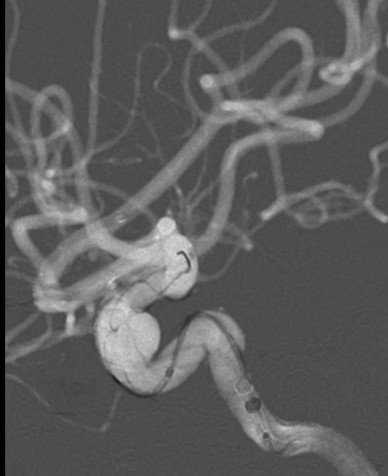

入院后行DSA检查明确右侧颈内动脉眼动脉后下方囊状动脉瘤样影,大小约1.09mm×6.53mm,宽基底,其下方见两个小囊状突起,左侧颈内动脉眼动脉后方及虹吸段均可见小囊状突起。考虑颅内多发动脉瘤。

锚定后,整体回撤至合适位置后,通过张力释放法缓慢释放支架,直至支架完全打开。观察见支架贴壁良好,动脉瘤颈完全覆盖,遂完全释放支架。

全脑DSA正侧位造影示血流通畅。

动脉瘤内造影剂滞留,未填弹簧圈。行Xper CT,观察见支架完全打开,贴壁良好。术程顺利结束。